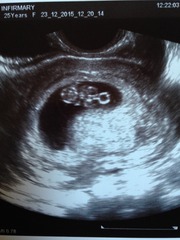

Christine my first scan ^ (on the left) was 7+3 and it is a bit blob-like tbh, but she struggled to get a decent shot. Think baby was at a funny angle! The pic on the right was 8+3 by my dates and the difference is huge!